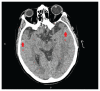

Traumatismes craniocérébraux et médullaires chez une piétonne heurtée par une trottinette électrique